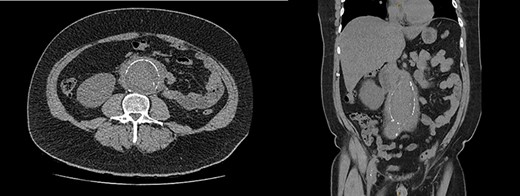

Urgent ureteric stenting to treat ureteric obstruction was performed with rapid normalization of renal function following stent insertion (Fig. 2). Upon normalization of his renal function, a contrast CT aortogram (CTA) was performed to delineate a 61 × 64 mm AAA, bilateral common iliac aneurysms (right 41mm × 44mm, left 31mm × 36mm) and associated peri-aortic stranding (Fig. 3).

CTA demonstrating (A) a large 61mm × 63mm infrarenal AAA and (B) bilateral common iliac aneurysms (right 41mm × 44mm, left 31mm × 36mm).